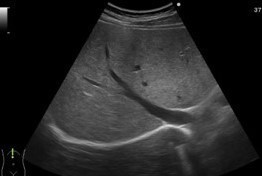

腹部超音波(エコー)検査は体表からプローベを当てて、超音波を深部に伝え、その反射具合により臓器や病変を確認する検査です。

プローベと体表の接触点にゼリーを塗布し、エコーのノイズを減らし、症状のある個所やスクリーニングを行っていきます。

細かくチェックしていきます